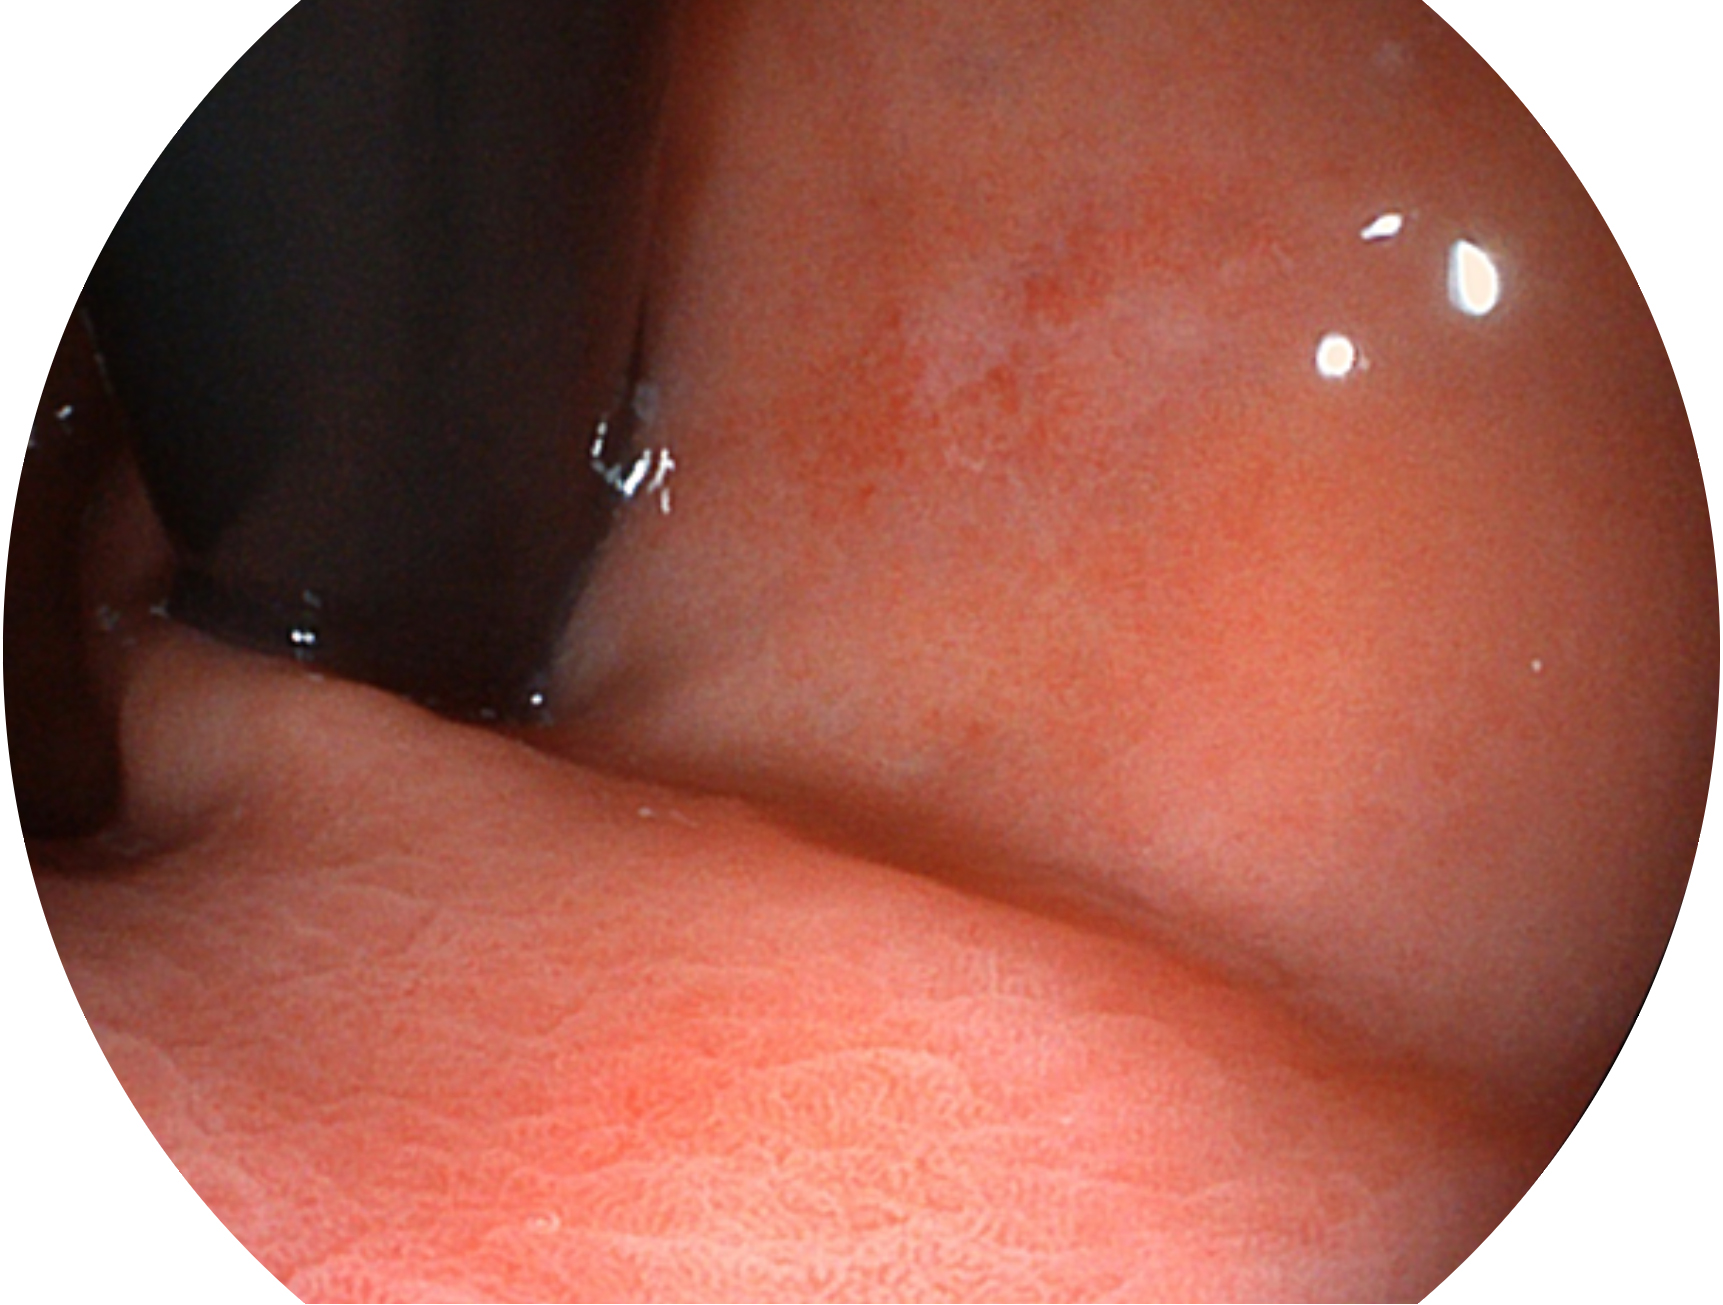

哈哈体育官网新开发的内镜染色技术,主要是基于多波长LED 光源的开发,VLS-55Q 四波长LED 光源是由四个不同颜色的LED光按照相应照明模式所规定的特定发光比例进行合束后形成,合束后形成的照明光的光谱由红光、绿光、蓝光及蓝紫光这四个不同的波段范围构成。具有更高光谱自由度,通过光谱比例的控制,实现了聚谱成像技术,英文全称为“Spectral Focused Imaging, SFI”,缩写为“SFI”和光电复合染色成像技术,英文全称为“Versatile Intelligent Staining Technology, VIST”,缩写为“VIST”。